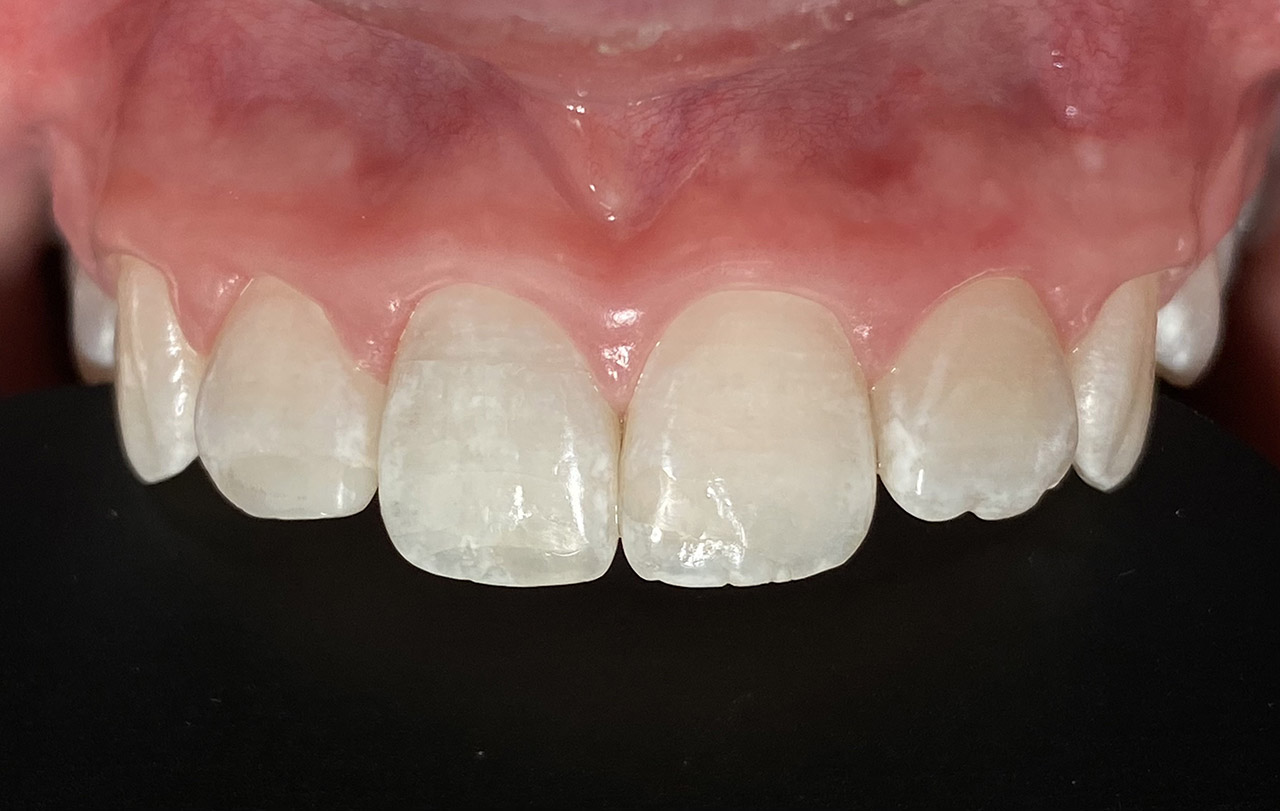

Aplasien/Nichtanlagen, dadurch bleibende Milchzähne, Diasteme/Zahnlücken,

Bleaching/Bleichen, Positionierung der Zähne/Kieferorthopädie (Dr. Maija Eltz), Verblendung mit Veneers/Keramikschalen.

Vorher Nachher